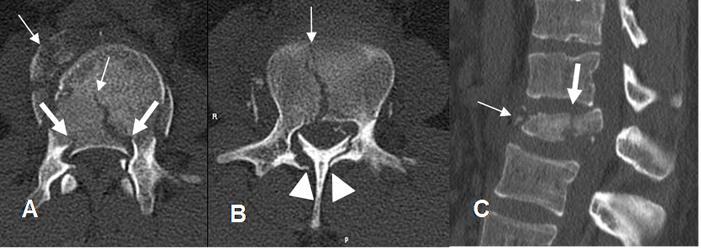

Fig 163. Fractura inestable.

A: TAC reconstrucción sagital, B: TAC axial y C: TM axial en T2. Fractura inestable con lesión de la columna anterior y media y fragmento retropulsado. (Flecha gruesa).